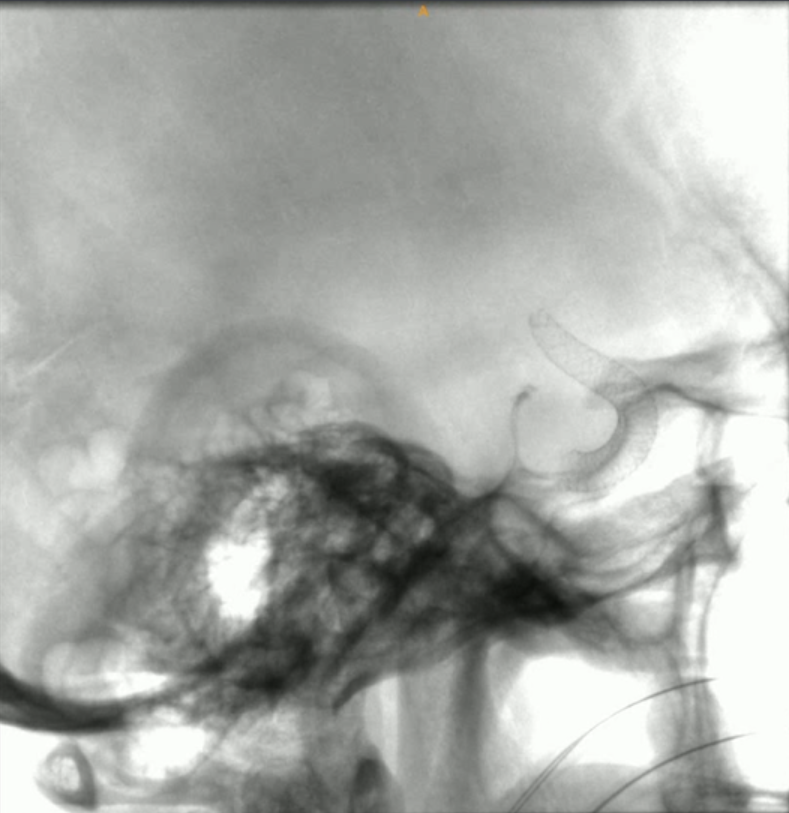

支架导管到位后,缓慢释放血流导向密网支架。

释放完全,即刻可见造影剂在动脉瘤腔内滞留

术中Dyna CT提示支架释放良好

术中影像融合提示支架贴壁良好

眼动脉,脉络膜前动脉,后交通动脉血流无影响

血流导向密网支架重建